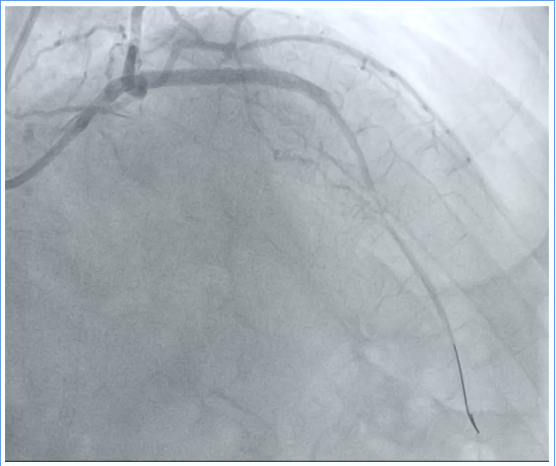

扩张后造影

图片图片